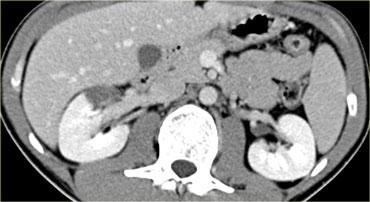

Trước tiên hãy quan sát các hình ảnh bên trái của bệnh nhân bị chấn thương gan.

Các dấu hiệu CT trong trường hợp này là gì?

Các dấu hiệu bao gồm:

- Mất tưới máu hoàn toàn thùy gan phải.

- Vùng ngấm thuốc cản quang (contrast blush) trong nhu mô gan, đồng thời lan ra ngoài bờ bên của gan.

- Tràn máu ổ bụng (Hemoperitoneum).

- Một vùng ngấm thuốc cản quang thứ hai ở mức thấp hơn.